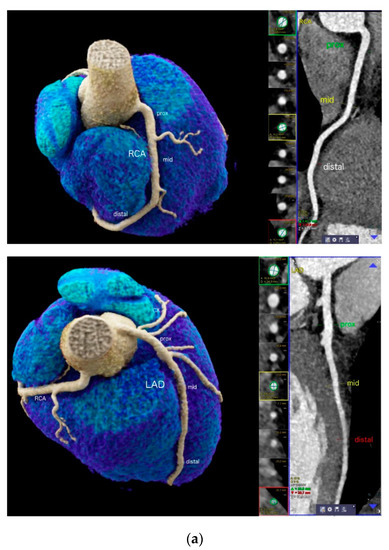

- Vessel size was measured using curved multiplanar reformations (cMPR) along a centerline on a cross-sectional perpendicular image, by a digital sizing tool in 2 dimensions (diameter 1 and 2) and effective vessel area, for each coronary segment using (AHA-modified-16-segment classification) [11] (Figure 1a). Vessel lumen was extracted automatically, and manual adjustments were made in case of outer lumen contour inaccuracies. The measurements were taken at a normal luminal site without coronary plaque, and the largest diameter was calculated. Segments with image quality limitations (e.g., artifacts, severe calcification) were excluded.